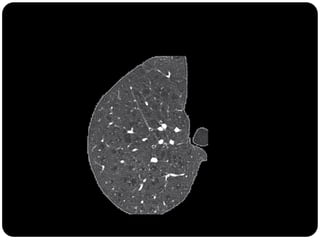

 Opacidade observada na TC, pode ser decorrente tanto de

alteração do espaço aéreo quanto do interstício.

 Alvéolos ou interstício ocupados parcialmente por processo

patológico (líquido, células, exudato); Resoluação da TCAR

não é suficiente para definir a imagem;